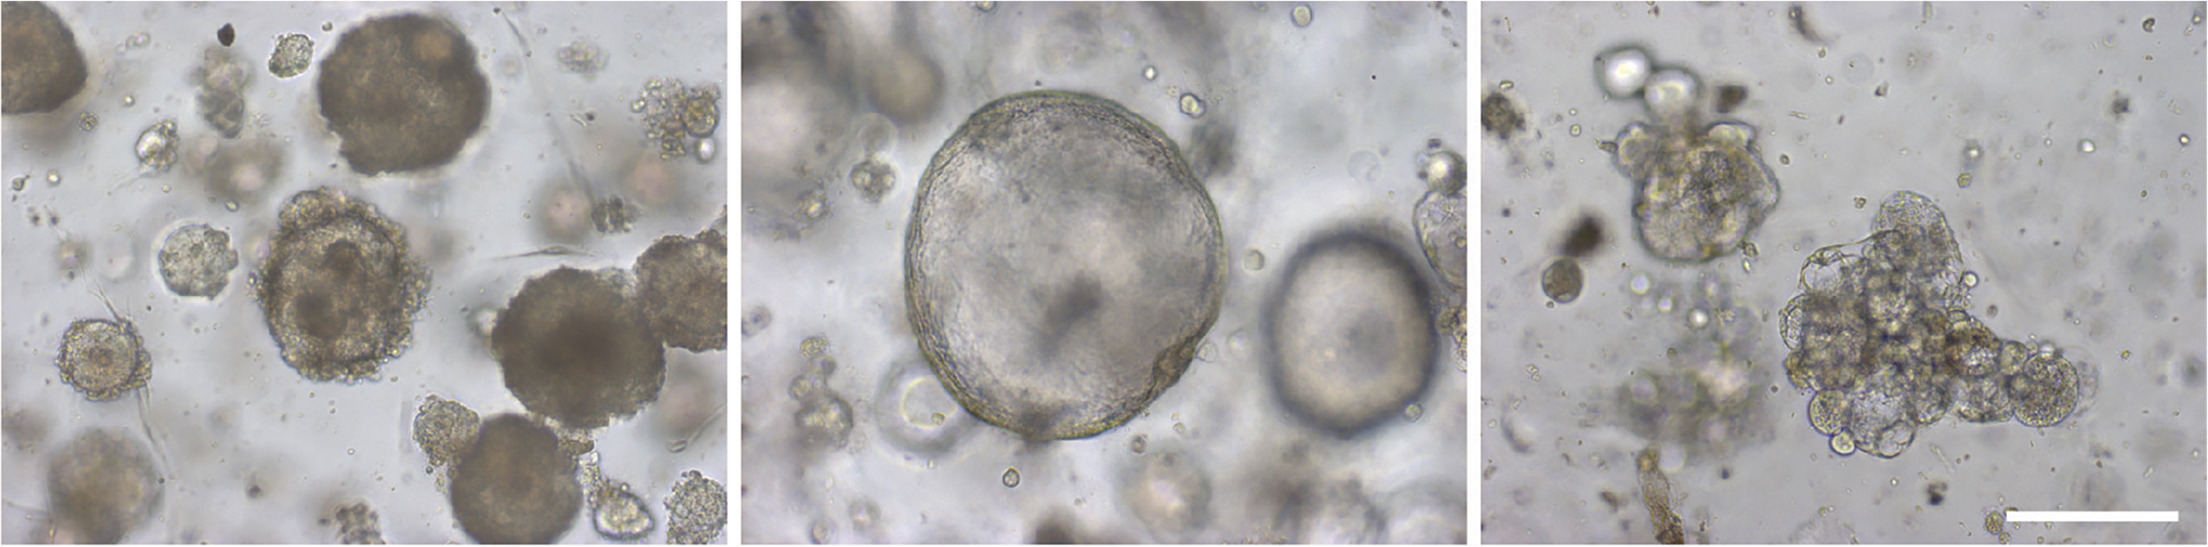

OC 类器官的不同形态表型。即致密(左),囊性(中)和低内聚(右)型 OC 类器官。比例尺 200 μm。

卵巢癌类器官样本来源不局限于活检样本或手术样本,腹水和胸腔积液中的癌细胞也同样可以用于构建 OC 类器官。培养成功的 OC 类器官经过 DNA 修复的功能性分析,可以准确预测患者对 DNA 修复抑制剂的临床反应。同时,OC 类器官也可以作为药物筛选的模型,通过分析个体患者来源的 OC 类器官对化疗药物敏感性的差异,来预测患者对特定药物的临床反应,从而选择针对患者的最佳治疗方案【7】。通过构建病人来源的 OC 类器官,对于更深入地了解卵巢癌的病因、发病机制、异质性和耐药性至关重要,并且对于确定新的治疗靶点和新药研发、患者用药决策方面都有着巨大的潜力。